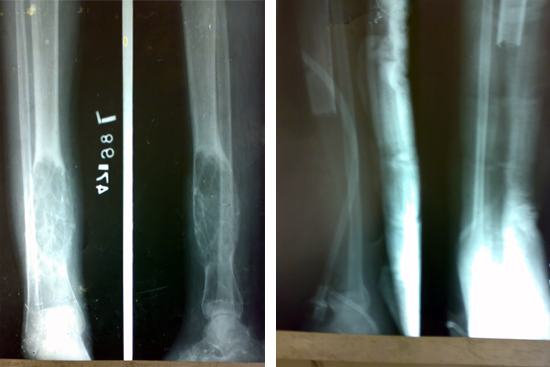

Tibialisation Of Fibula

Shankar Giri

Sudama

Wagh